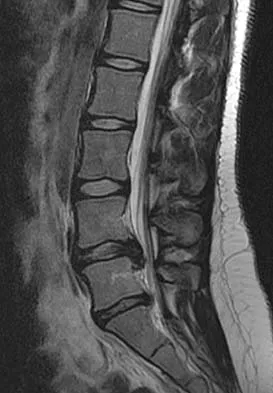

A 50-year-old man reports the onset of back pain and incapacitating pain radiating down his left leg posterolaterally and into the first dorsal web space of his foot 1 day after doing some yard work. He denies any history of trauma. Examination reveals ipsilateral extensor hallucis longus weakness. MRI scans are shown in Figures 19a through 19c. What nerve root is affected?

Detailed Explanation